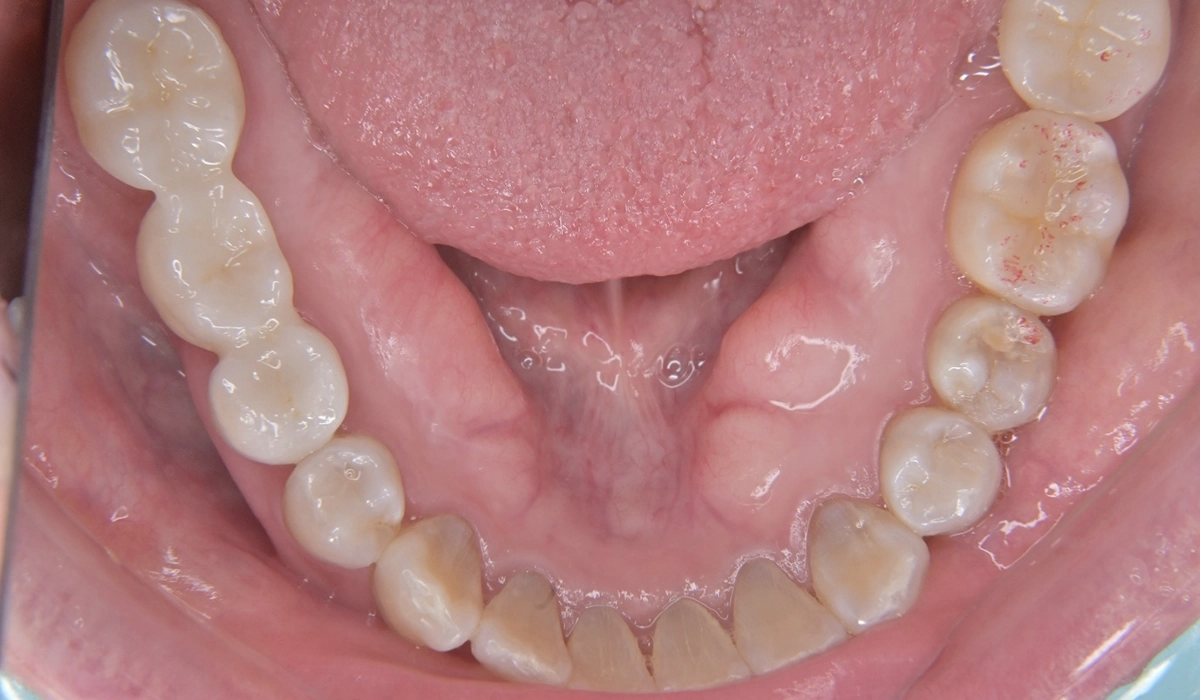

進行したカリエスと歯周病に対して全顎治療を行った症例報告です。

こちらが術前の口腔内写真になります。

問題点としては前歯部、臼歯部で進行したカリエスおよび前歯部歯肉増殖症、広範型慢性歯周炎StageⅡ GradeAが挙げられます。本症例では前歯部の審美性の回復について患者様との話し合いのうえセラミック修復による治療を選択しました。

治療のステップとして全顎的な歯周環境の改善のための歯周基本治療、前歯部の歯周形成外科、前歯部カリエスに対する根管治療、前歯部プロビジョナルレストレーションによる歯肉形態修正、最終補綴の順で治療を進めていきました。

歯周環境の改善のために親知らずの抜歯を適宜行っています。